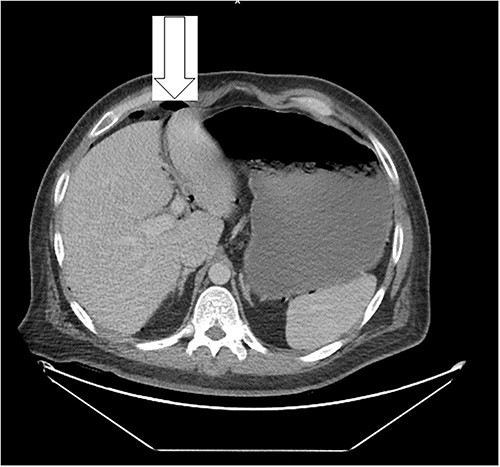

Ten days prior to ER admission, he presented to an outlying hospital with nausea, vomiting and diarrhea episodes and underwent a LC. A baseline computerized tomography scan (CT) demonstrated pneumoperitoneum (see Fig. 1). Because of the lack of inflammatory changes in the GI tract, viscus perforation was an unlikely consideration. An EL was performed that came back negative and he was subsequently discharged.